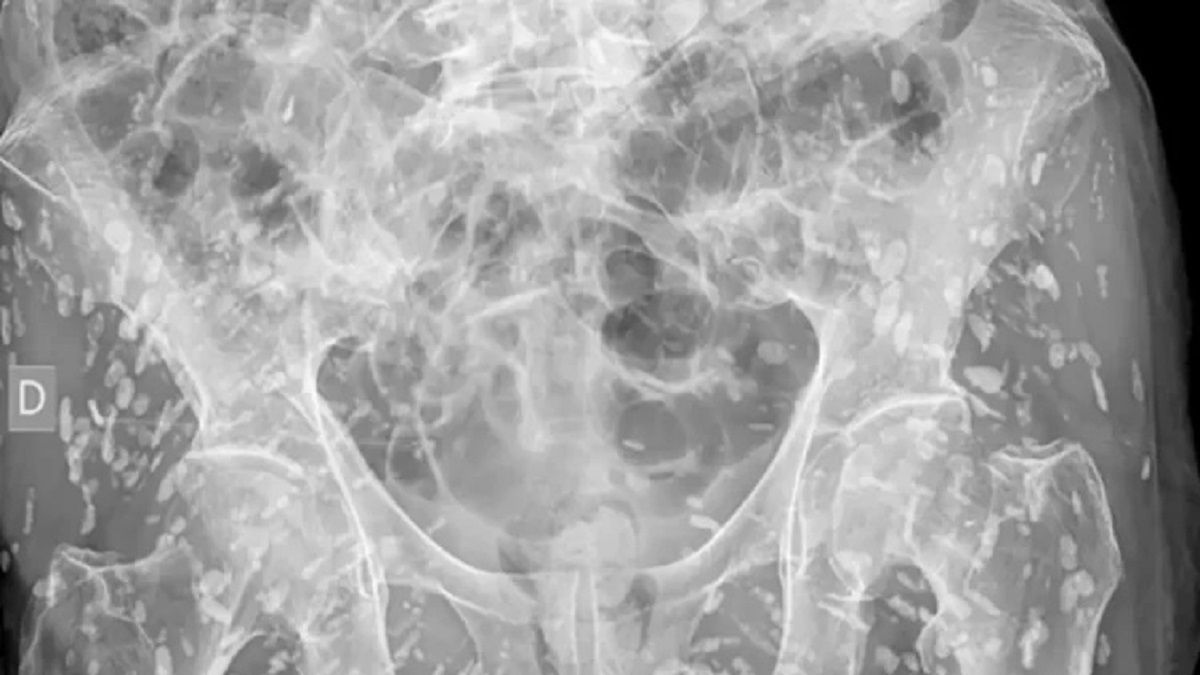

شارك أحد أطباء الطوارئ مؤخراً «واحدة من أكثر صور الأشعة السينية جنوناً التي شاهدها على الإطلاق»، إذ تُظهر الجزء السفلي من جسم شخص مصاب بمئات من بيوض الدودة الشريطية المتكلسة.

وشارك أحد أطباء الطوارئ مؤخراً «واحدة من أكثر صور الأشعة السينية جنوناً التي شاهدها على الإطلاق» كما ينقل عنه موقع «أوديتي»، والتي تُظهر الجزء السفلي من جسم شخص مصاب بمئات من بيوض الدودة الشريطية المتكلسة.

وقال إن الصورة جاءت بالصدفة لمريض كان يشكو من وجع في الورك، ناتج عن مشكلة عظمية، لا علاقة للبيوض بها.

وأكد الطبيب أن خطورة بيوض هذه الدودة الفعلية تكمن في وصولها للمخ ويمكن أن تسبب مشاكل جمة قد تنتهي بالموت.